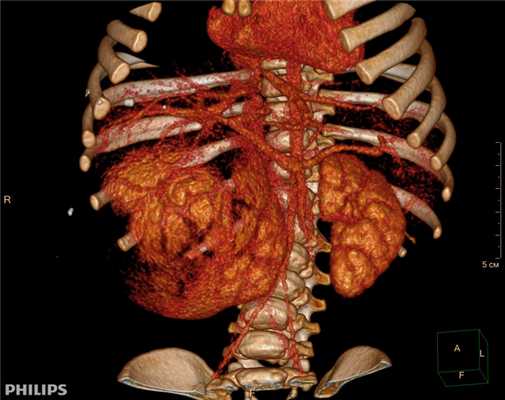

3D-реконструкции опухоли Вильмса пациентов детского отделения НМИЦ онкологии им. Н.Н. Петрова

Опухоль Вильмса. Компьютерная томография